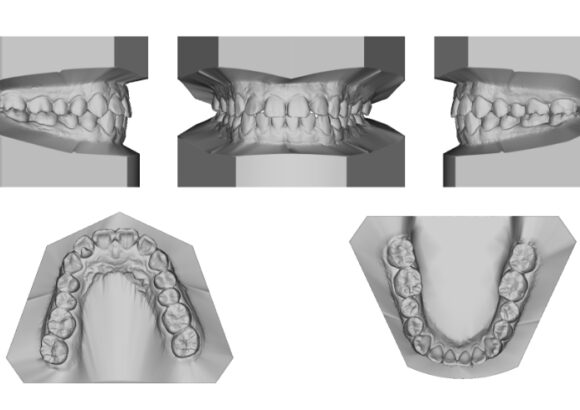

El escaneo dental es un dispositivo digital utilizado para capturar impresiones tridimensionales de la boca del paciente.

Este tipo de escaneo permite recrear la dentadura con una precisión que supera con mucho las muestras tomadas con materiales de impresión tradicionales.

• Réplica exacta de las estructuras dentales y tejidos adyacentes del paciente.

• La ventaja es que su consulta se actualiza dejando atrás modelos de yeso que se rompen o maltratan y que además debe de almacenar. Le damos la alternativa de almacenarlos digitalmente teniéndolos virtualmente en su computadora y si requiere imprimirlos podemos realizarlo en el momento que necesite.

• Los escaneos son considerados tan precisos si no más exacto que los moldes de yeso. El proceso de escaneo es más cómodo para pacientes especialmente con reflejo nauseoso.

Escaneo guías quirúrgicas

• Mayor precisión comparado con modelos convencionales de alginato, sin necesidad de repetir la toma de impresión.

• Comodidad para pacientes con reflejos de nauseas.

• Envío inmediato del registro.